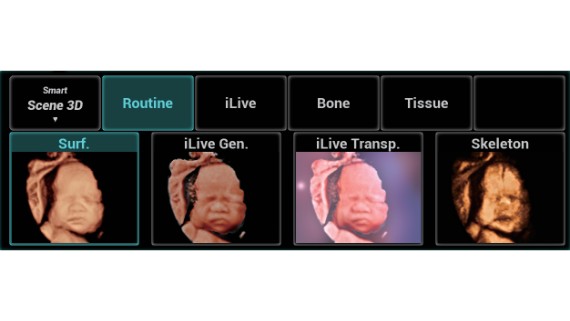

Full-stack Solution Powered by ZST?+

The ZST+ platform is an extraordinary innovation, representing an ultrasound evolution. Transforming ultrasound metrics from conventional beam-forming to channel data based processing. It overcomes the traditional trade-off limitation among spatial resolution, temporal resolution and tissue uniformity, delivering exceptional image quality for infinite imaging solutions with non-stop improvements.